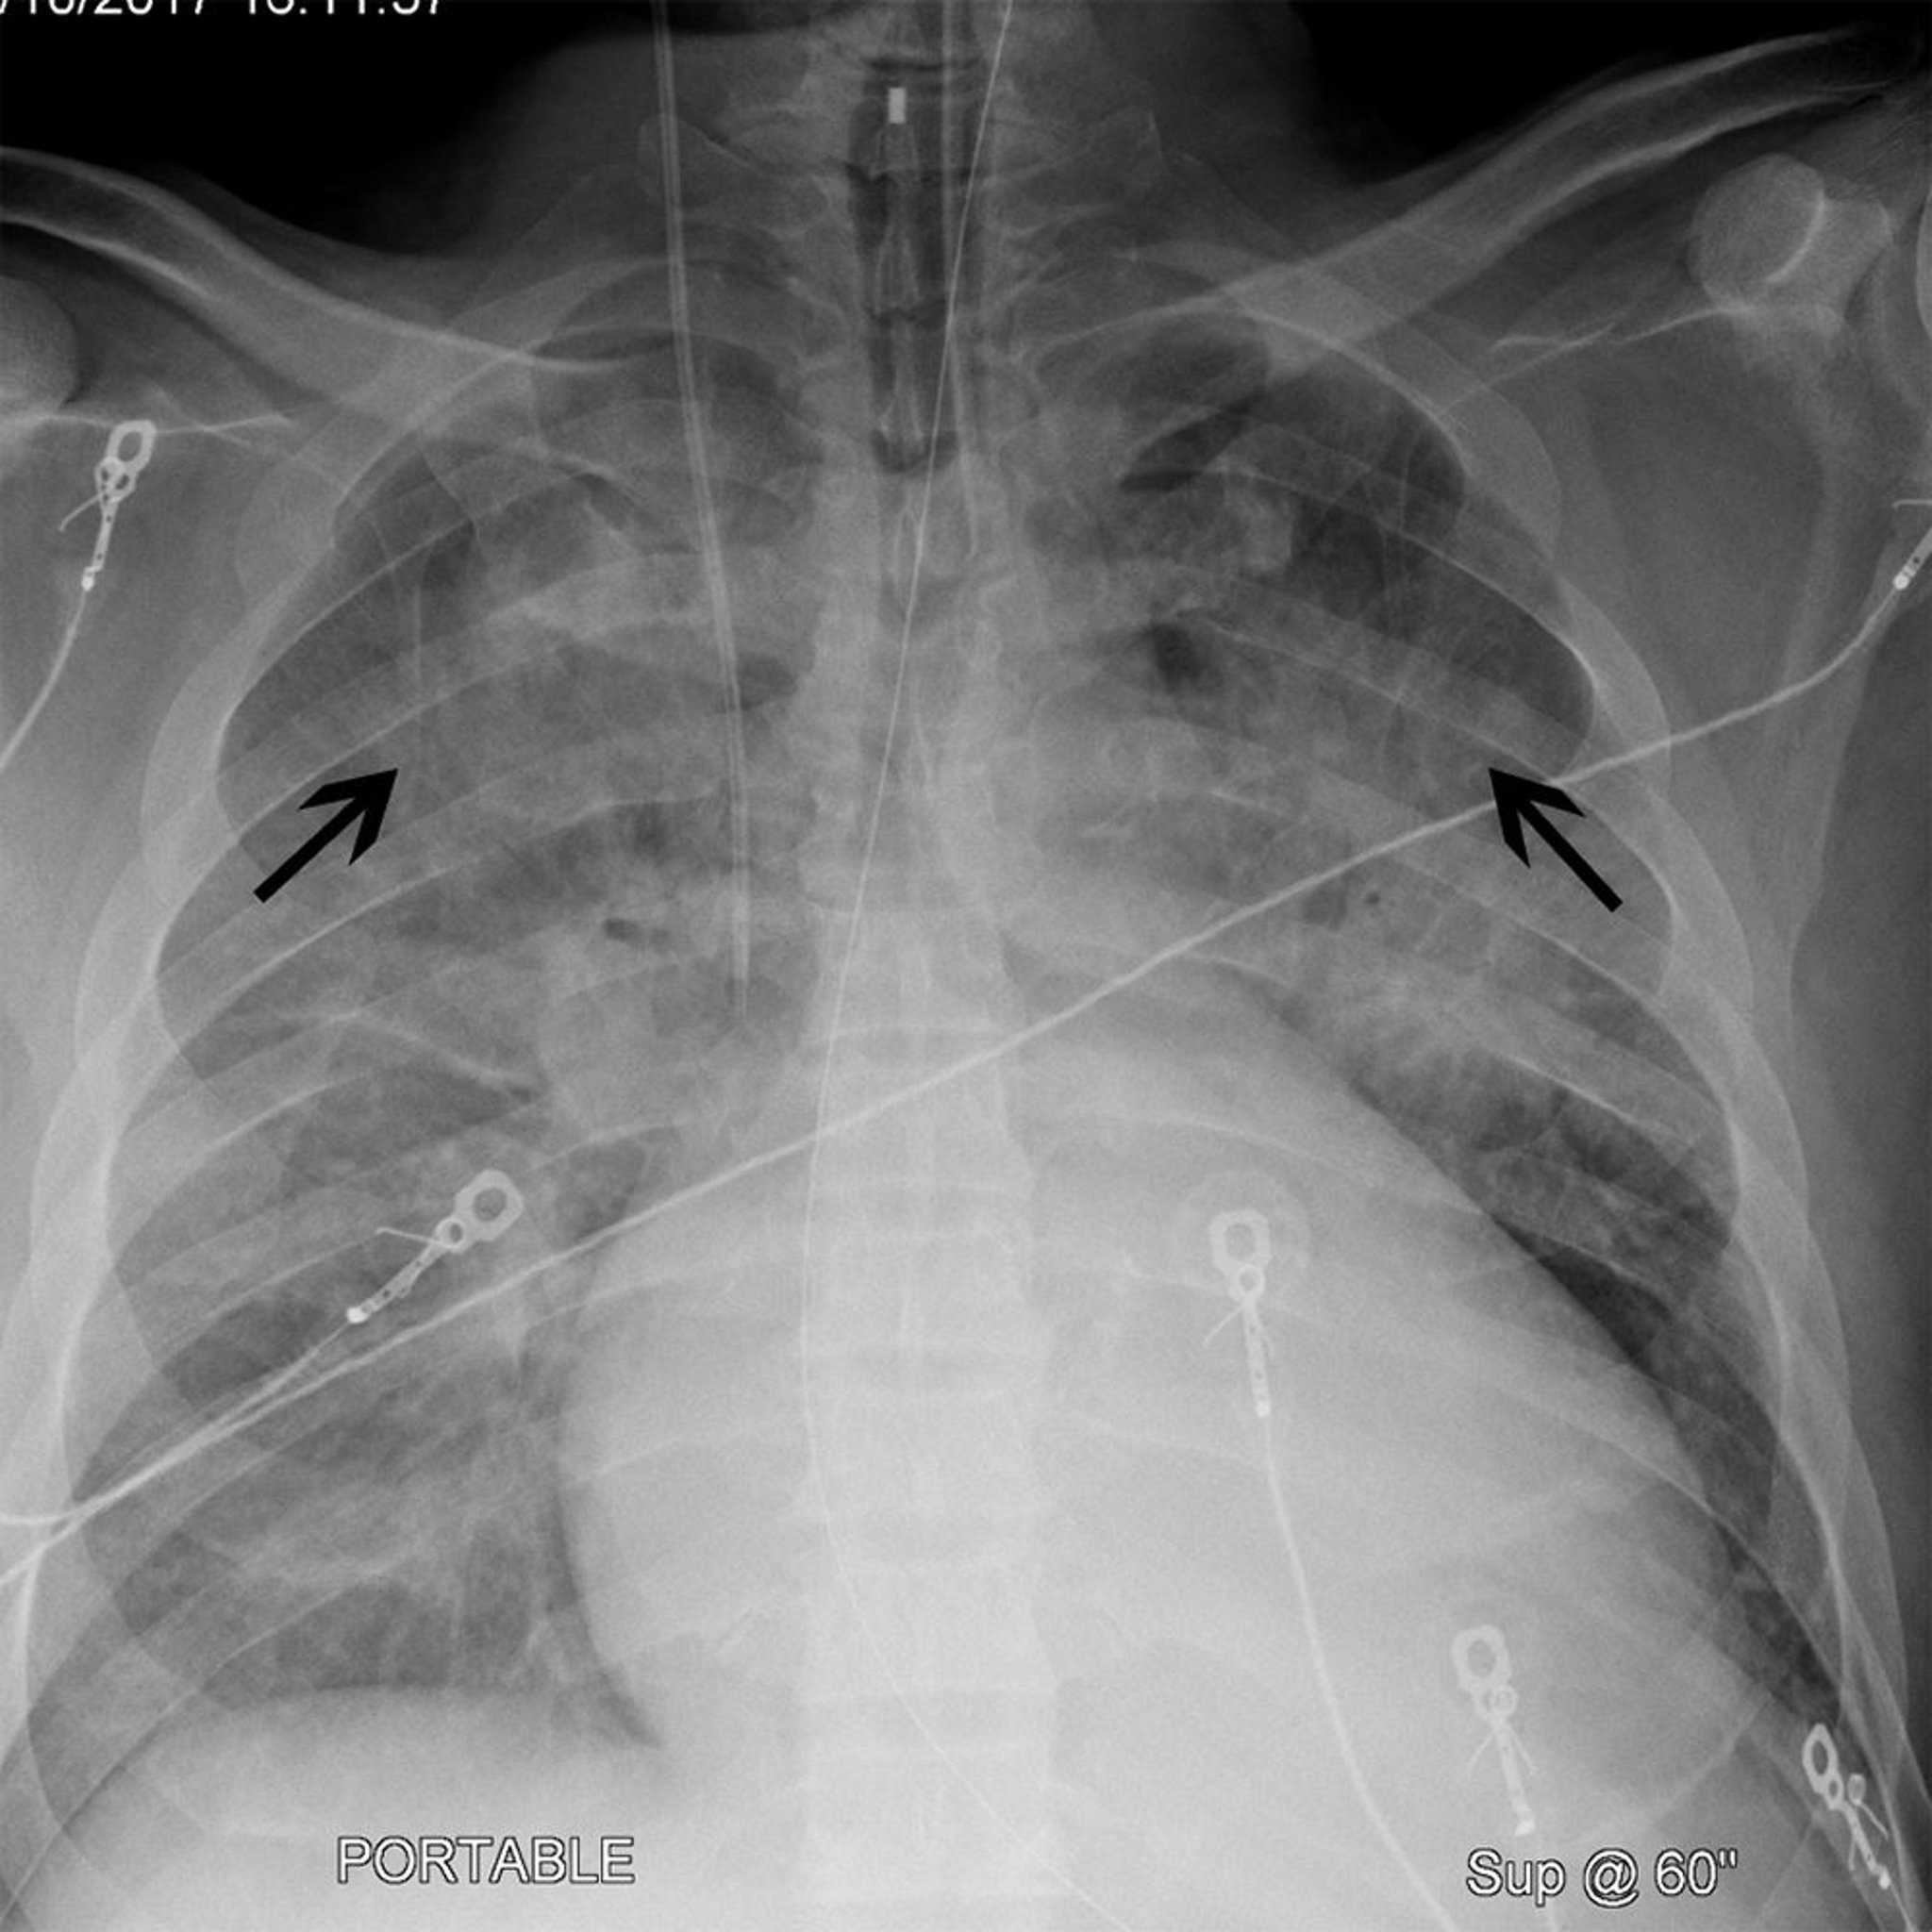

Radiographie pulmonaire d'un patient présentant une cardiomégalie et une céphalisation

Ce patient a une cardiomégalie (largeur de la silhouette cardiaque est > 50% de la cage thoracique sur une radiographie de thorax de face). Le patient présente également une céphalisation (flèches noires) par laquelle les vaisseaux pulmonaires du lobe supérieur deviennent plus visibles. Ces signes sont souvent observés en cas d'insuffisance cardiaque.